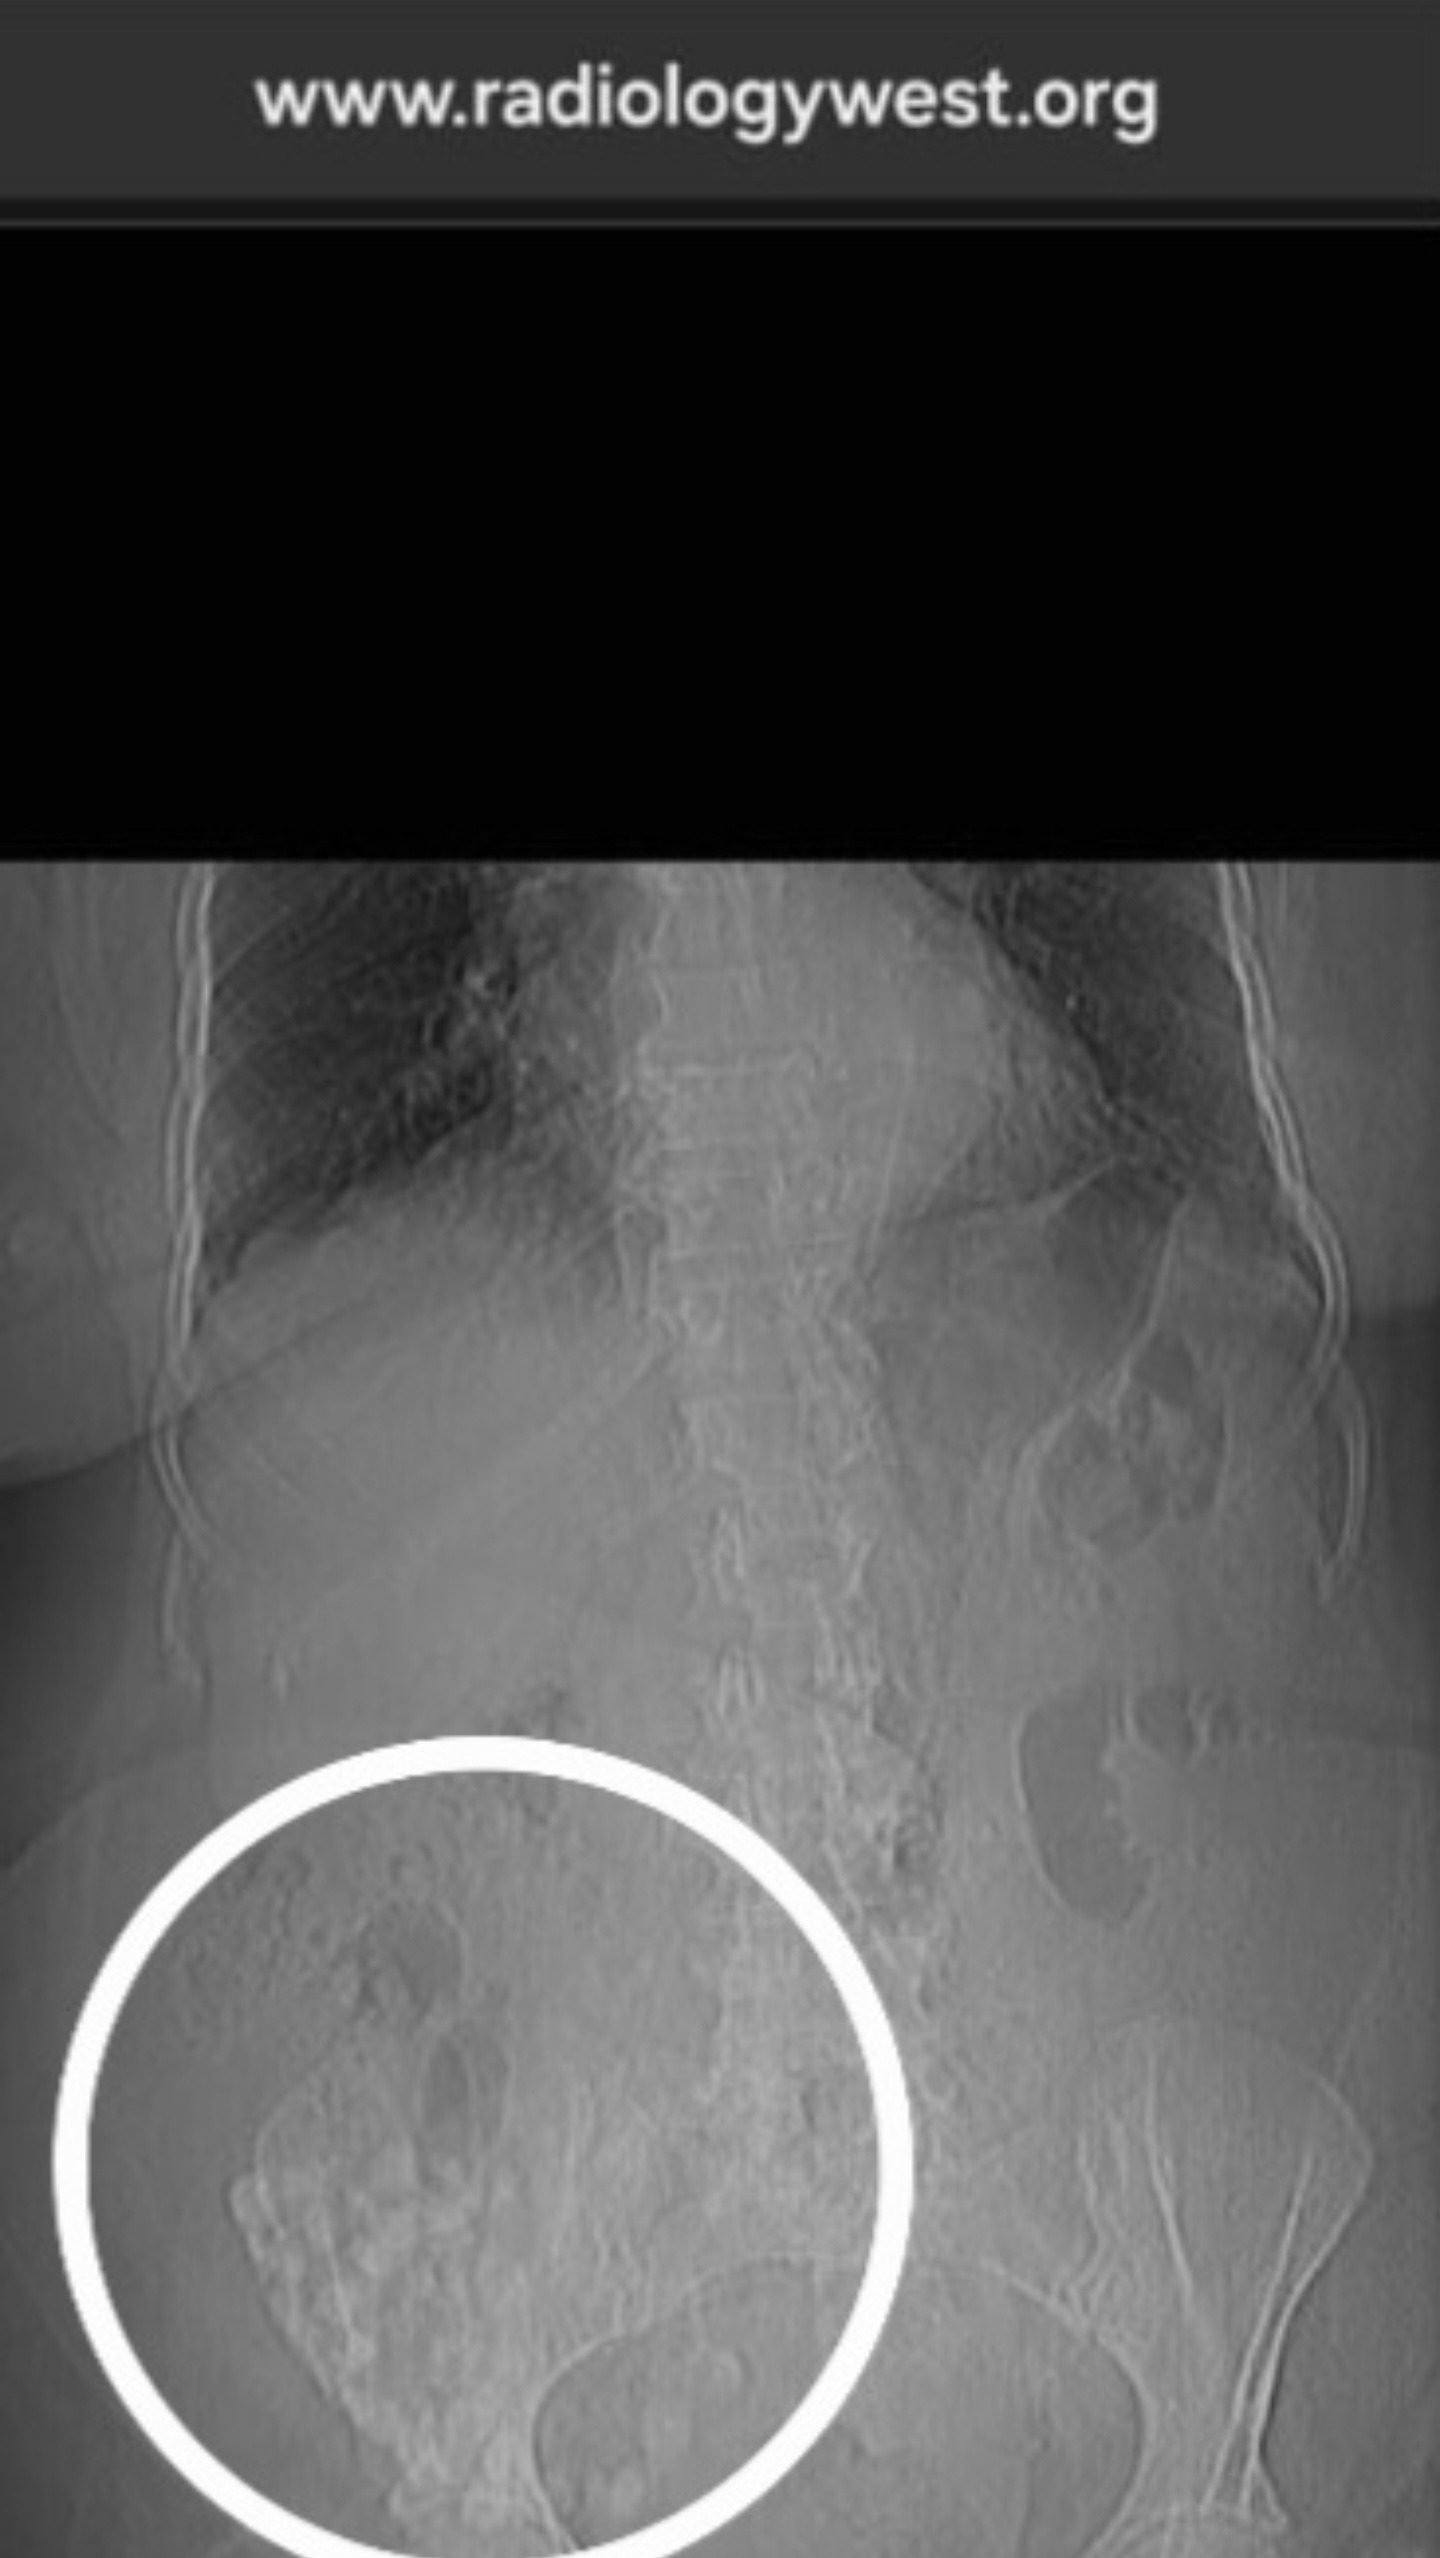

So far, Grace has undergone multiple tests, including MRIs, a colonoscopy, and CT scans. As her illness progresses, even more tests—and possibly surgery—are needed to determine exactly what is going on and how best to treat her.